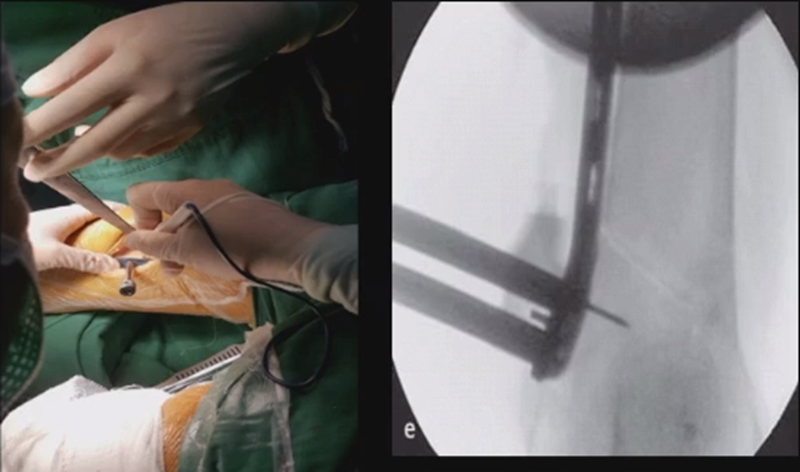

合页点和截骨线已确定好,按照术前计划打入导针,测量截骨深度。

注意,目前临床推荐的DFO要求最好能做双平面截骨,即还要有一条上行截骨线,上行截骨线与水平截骨线夹角大概为95° 左右。这种截骨方式一方面可以增加稳定性,同时也可以减少对上方髌股关节的干扰。

上行截骨时,要保持肢体旋转中立位,前方要有骨撬保护,由内向外完全截开,上行截骨线不存在合页。

水平截骨时,同样放肢体中立位,后侧放一把骨撬保护后方重要结构。

截骨过程中,不要求一次截骨到位,把合页深度全部截到,可以留最后一点,用钻头由前向后打出一排筛孔来,把合页端弱化,再去做闭合时就不容易折断了。